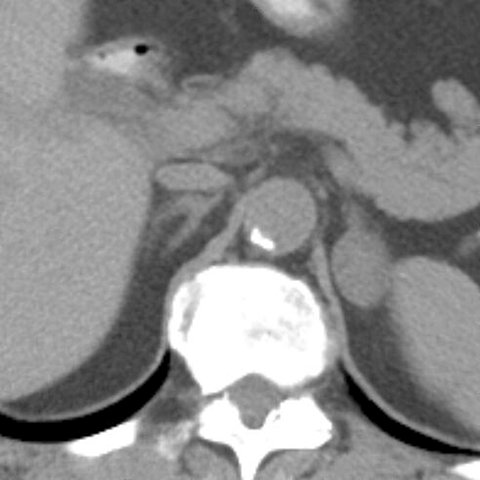

24-year-old-female presents with a 2 year history of an abdominal mass [1 of 3]